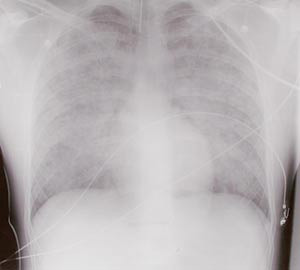

Røntgen thorax viste uttalte ulne, spredte fortetninger bilateralt (fig 1). Transøsofageal ekkokardiografi viste hyperdynamisk sirkulasjon, ingen klaffefeil og normal kontraktilitet. Tilkoblet respirator fikk han 100 % oksygen, og han ble behandlet med et høyt positivt endeekspiratorisk trykk (PEEP). På tross av dette var han alvorlig hypoksisk og hadde metabolsk acidose. Han var også hypotensiv (60/40 mm Hg), og det ble startet med væske- og vasopressorterapi. På bakgrunn av manglende behandlingsrespons ble han etter hvert snudd i mageleie. Dette bedret oksygeneringen.

De vanlige symptomer og funn ved heroinoverdoser er relatert til opiateffekten slik som nedsatt bevissthet, nedsatt respirasjonsfrekvens og miotiske pupiller. Ved fullt utviklet lungeødem kan pasienten ha skummende rødt ekspektorat og være cyanotisk. Symptomer på lungeødem kommer vanligvis innen 1 – 2 timer, sjeldnere innen fire timer etter inntak. Ved mildere tilfeller kan man ofte påvise nedsatt perifer oksygenmetning til tross for normal eller økt respirasjonsfrekvens. Foreslåtte diagnosekriterier er sO₂(a) under 90 % uten tilførsel av oksygen, normal eller økt respirasjonsfrekvens, opptreden innen ett døgn etter en heroindose og røntgenologiske lungeinfiltrater uten andre kjente årsaker (4). Infiltratene er vanligvis bilaterale, spredte og ulne. Unilaterale infiltrater kan forekomme. Arteriell blodgassanalyse vil som regel vise acidose, hypoksi og varierende grad av hyperkapni. Grad av sirkulatorisk påvirkning vil variere med grad av sympatikushemning. De dårligste pasientene vil ofte ha hypotensjon med en kompensatorisk takykardi. Man vil finne et lavt sentralt venetrykk, moderat forhøyet lungearterietrykk og normal lungekapillarmotstand (8).